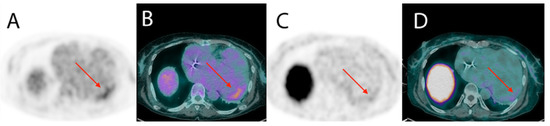

- Garg, G.; Cohen, S.; Neches, R.; Travin, M.I. Cardiac (18)F-FDG uptake in chagas disease. J. Nucl. Cardiol. 2016, 23, 321–325. [Google Scholar] [CrossRef]

- Shapiro, H.; Meymandi, S.; Shivkumar, K.; Bradfield, J.S. Cardiac inflammation and ventricular tachycardia in Chagas disease. HeartRhythm Case Rep. 2017, 3, 392–395. [Google Scholar] [CrossRef] [PubMed]

- Moll-Bernardes, R.J.; de Oliveira, R.S.; de Brito, A.S.X.; de Almeida, S.A.; Rosado-de-Castro, P.H.; de Sousa, A.S. Can PET/CT be useful in predicting ventricular arrhythmias in Chagas Disease? J. Nucl. Cardiol. 2020, 1–4. [Google Scholar] [CrossRef] [PubMed]